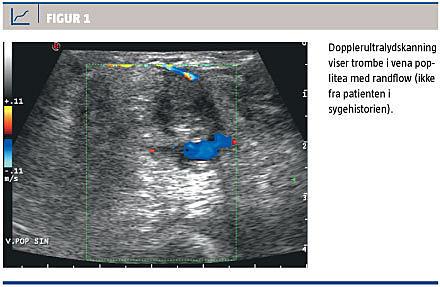

En 24-årig rask mand fik rødme og hævelse af højre ben og blev af en vagtlæge sat i behandling med penicillin-V på mistanke om erysipelas. Dagen efter opstod der forværring med smerter og hævelse af læggen, hvorfor han af egen læge blev henvist til et sygehus på mistanke om dyb venøs trombose (DVT). Der blev udført ultralydskanning af benets venesystem, hvor man konstaterede trombemasser i vena femoralis og vena poplitea (Figur 1). Patienten blev sat i behandling med heparin, lang kompressionsstrømpe og K-vitamin-antagonisten phenprocoumon, hvorved man opnåede international normaliseret ratio (INR) i det ønskede terapeutiske interval på 2-3.